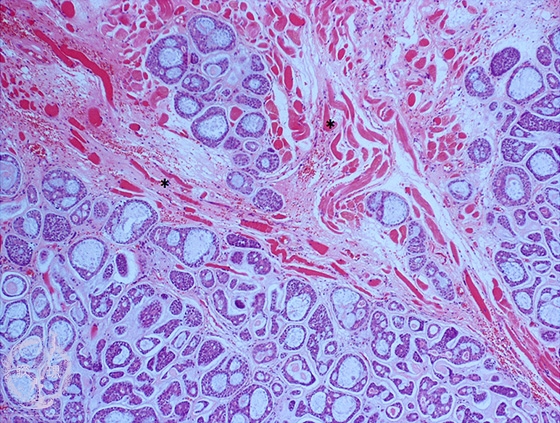

- (7)Salivary gland tumor(★adenoid cystic carcinoma)

Microscopic finding (HE stain, low-power view):Cribriform and tubular nests infiltrate into the muscle (*).